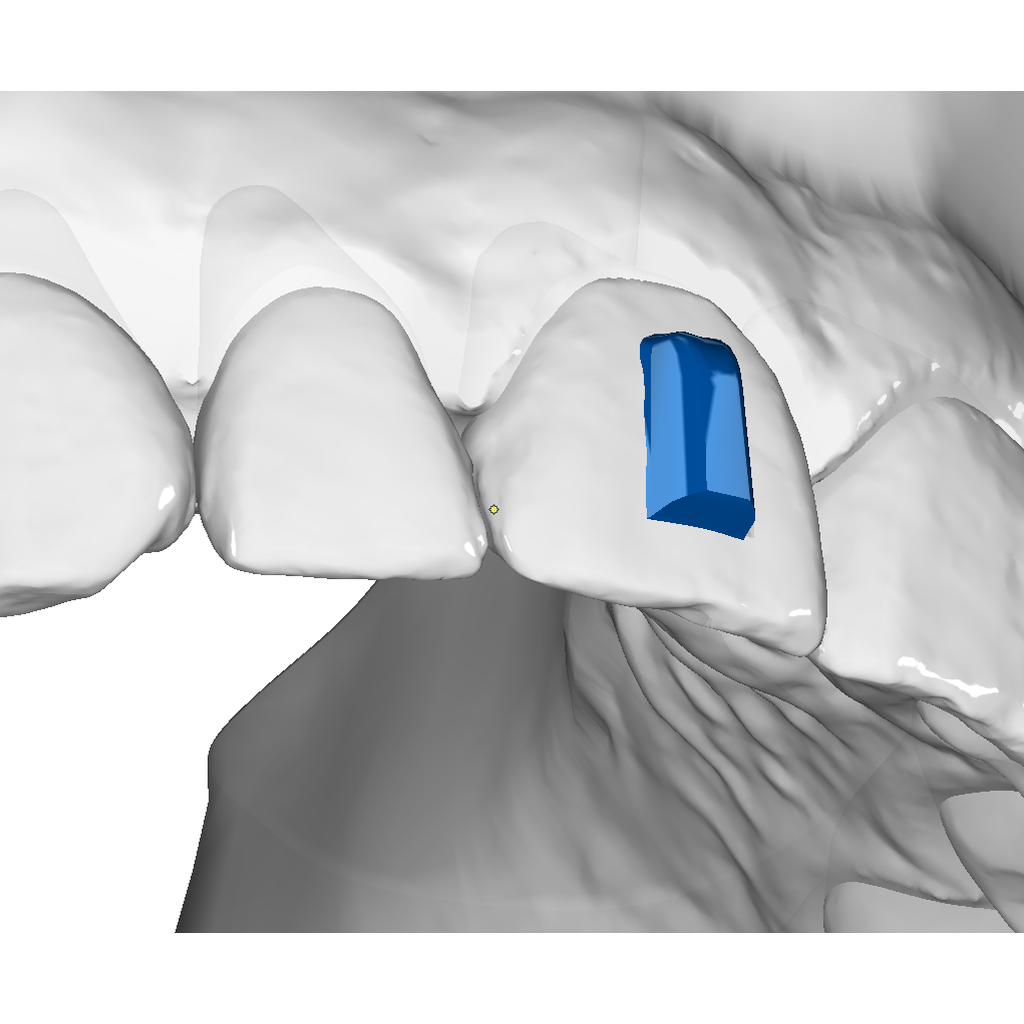

Vertical Attachment Template for Aligner Therapy

The vertical attachment is the workhorse of aligner biomechanics. Its vertical orientation provides the leverage needed for derotation, full bodily movement, and demanding distalization sequences — making it an essential part of any comprehensive aligner case.

✔ Derotation & bodily movement — vertical geometry delivers the control needed for complex 3D tooth movements

✔ Semi-sequential distalization — reliable anchorage for staged posterior movement

✔ Four size options — from 3×2 mm to 6×3.5 mm to match any tooth and indication

✔ Digital O3P template — ready to place directly in OnyxCeph